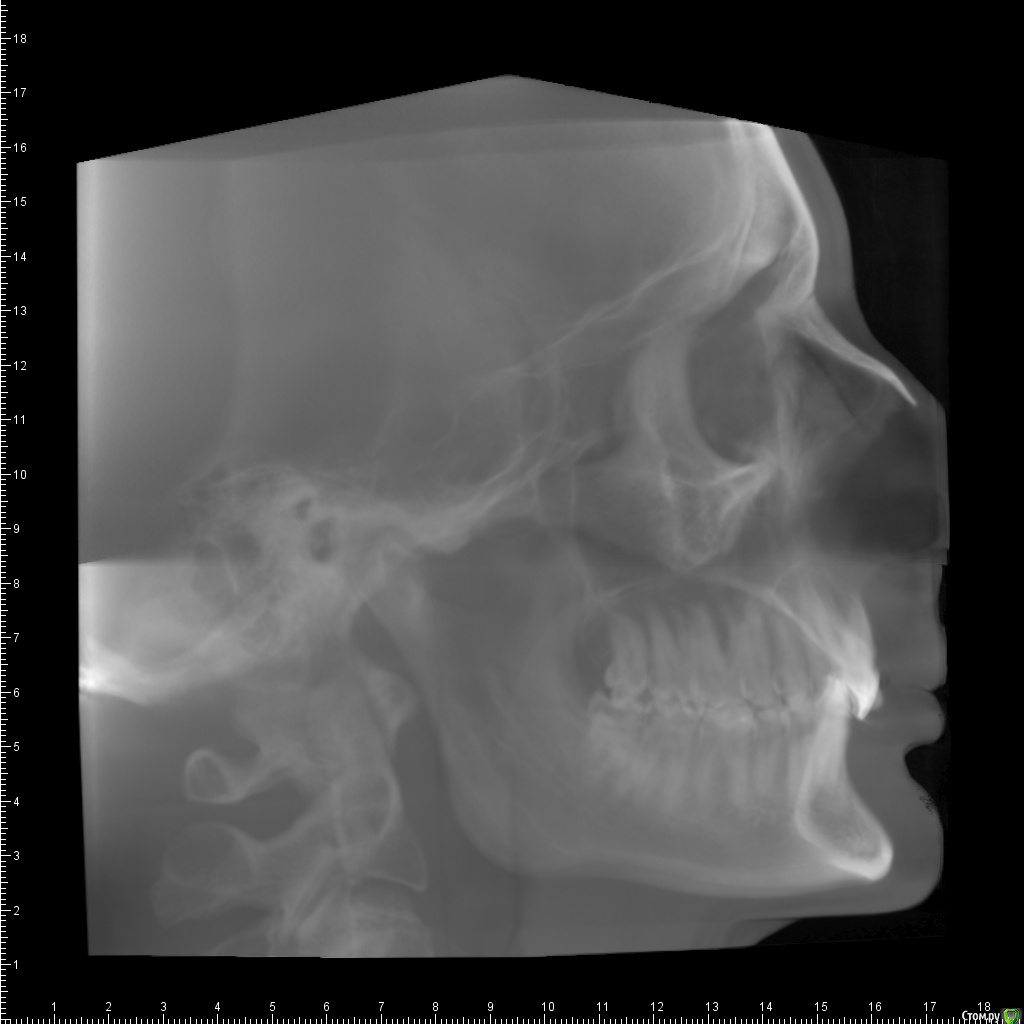

Беспокоит: Возраст 30 лет.  с 15 лет щелчки в суставе, полгода назад появилась периодическая боль - в области сустава, напряжение в жевательных мышцах, в шее  (с шеей вообще давние проблемы - не знаю, что первопричина болей), боли в затылке, голове. Глубокий прикус. Решил прикус исправлять в надежде, что боли уменьшатся.  На снимках видно, что челюсть нижняя заблокирована в заднем положении, мешают верхние резцы, головка сустава смещена

Частичное переднее смещение суставного диска ВНЧС справа в положении с закрытым ртом, полная репозиция диска в положении с открытым ртом. Частичное переднее смещение наружного отдела суставного диска ВНЧС слева в положении с закрытым ртом (за счёт внутренней ротации диска), полная репозиция диска в положении с открытым ртом. Остеоартроз ВНЧС справа 1 ст.